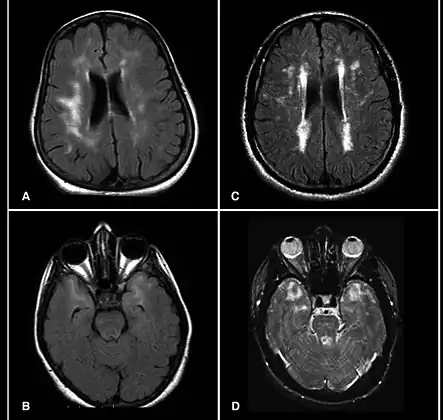

MRI demonstrating white matter changes in the brain of patients with CADASIL

CADASIL is an inherited disorder caused by mutations in the NOTCH3 gene located on chromosome 19.[19] NOTCH3 codes for a transmembrane protein whose function is not well-known. However, the mutation causes accumulation of this protein within small to medium-sized blood vessels.[19] This disease often presents in early adulthood with migraines, stroke, mood disturbances, and cognitive deterioration. MRI shows white matter changes in the brain and also signs of repeated strokes. The diagnosis can be confirmed by gene testing.[20]